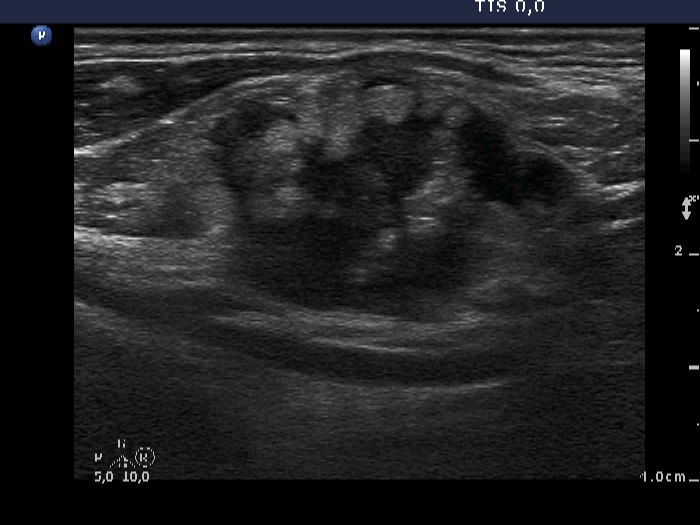

Ultrasonography: the thyroid was intact. There were multiple nodes in both supraclavicular regions. The nodes presented an absolutely irregular shape and border. They contained numerous hyperechogenic circumscribed areas.

Cytology was performed from the masses and resulted in anaplastic adenocarcinoma of unknown origin.

Further evaluation of the patient revealed a mass in the lower right lobe of the lung . Percutaneous lung biopsy disclosed anaplastic adenocarcinoma of the lung.